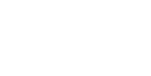

Tonsillektomi Nedir? Bademcik ameliyatı ya da tonsillektomi, bademciklerin ameliyat ile çıkarılması işlemidir. Bademcikler, dilin arka kısmında ve boğazın iki yanında bulunan organlardır. Bademcikler bakteri ve virüs gibi mikroorganizmalara karşı antikor üreterek vücudun savunmasına katkıda bulunur. Bademcikler vücut için faydalı olmakla birlikte, normalden büyük olması ya da iltihaplanması durumunda çeşitli sorunlara neden olabilmektedir. Sık geçirilen bademcik…

- Tonsillit: Bademcik iltihabıdır. Boğaz ağrısı, yutma güçlüğü, ateş gibi belirtiler görülebilir.